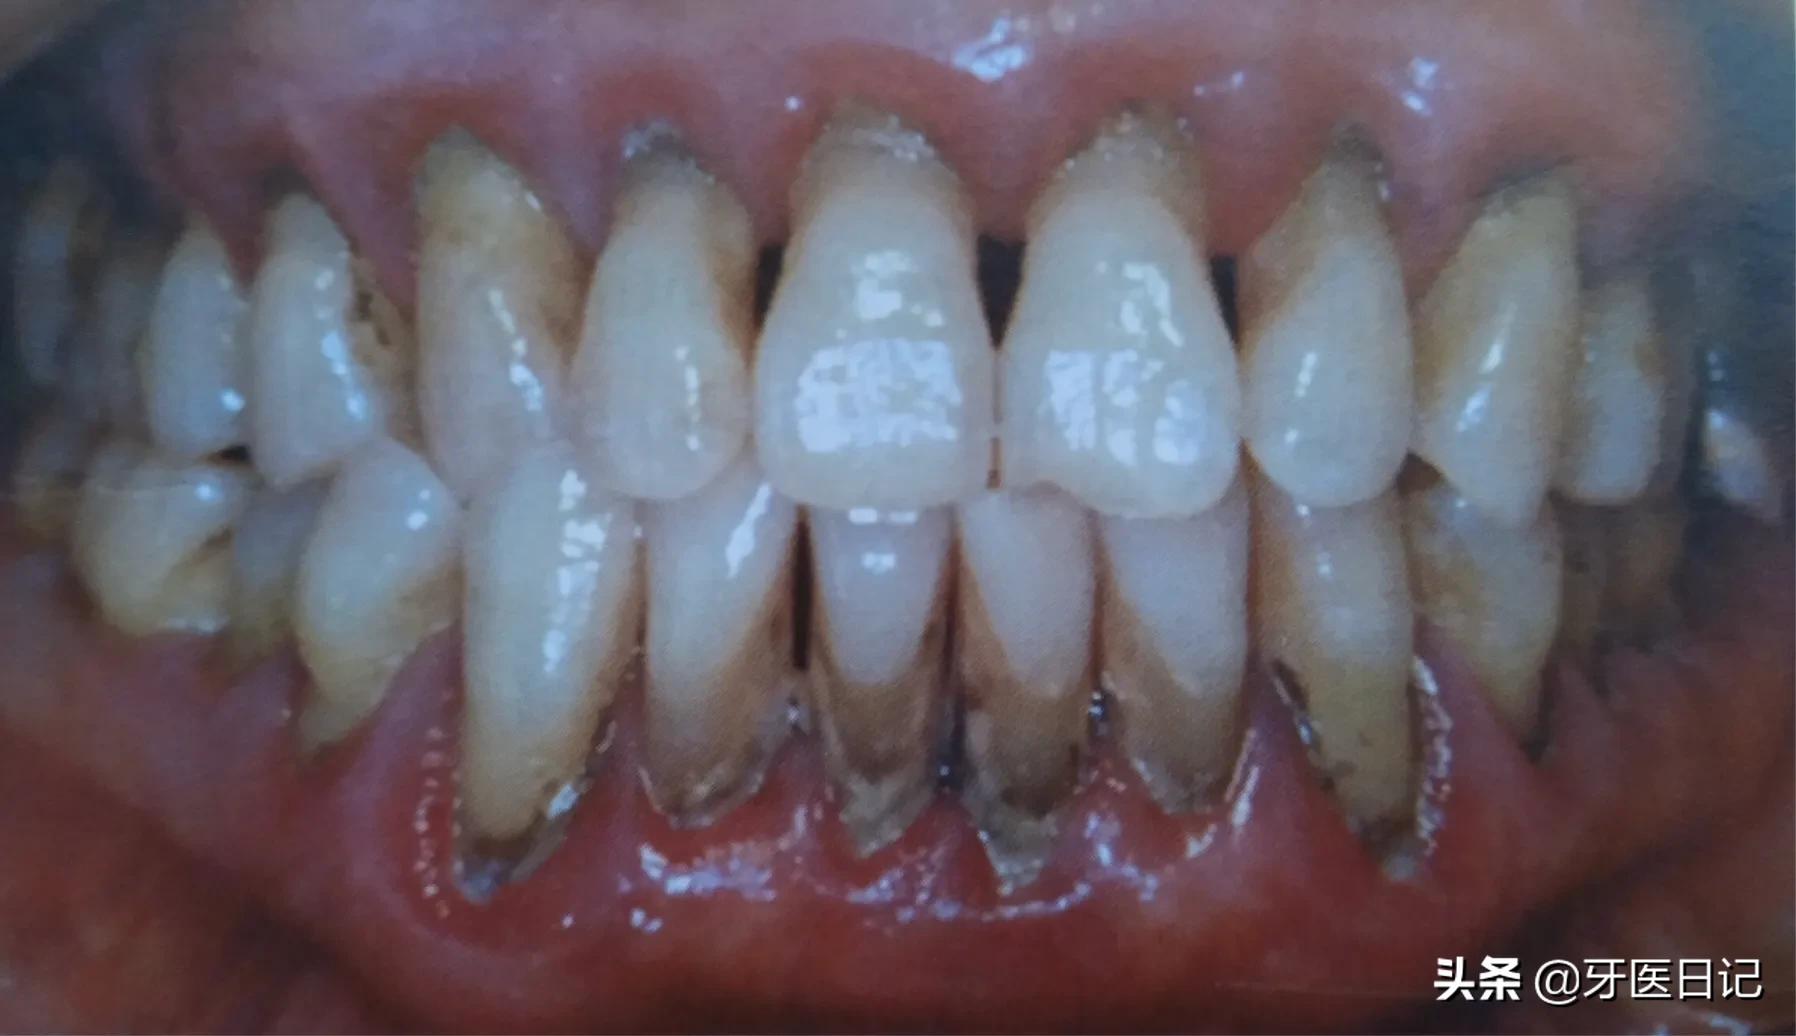

②牙周炎:主要表现牙齿的松动、移位,牙龈出血,牙槽骨的吸收,同时会伴有牙周袋溢脓口臭等表现

一部分牙龈炎的患者得不到及时治疗,炎症可向牙周深部发展,导致牙齿周围的支持丧失,比如牙齿周围的骨头,随着病变继续向牙根发展,逐渐出现牙齿松动移位,牙龈萎缩,急性肿胀疼痛。